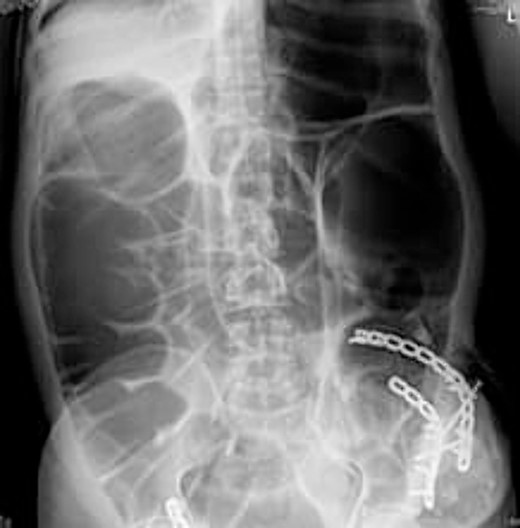

Radio imaging was requested for the patient at admission. Erect X.R. has been taken, showing dilated bowel loops (Figs 3 and 4).

The preferred imaging method is computed tomography. While ultrasound is a low-cost, low-risk alternative for assessing these hernias, it does not reveal concomitant abdominal illness and is used less frequently in clinical settings [22, 23]. Conventional X-rays revealed dilated bowel segments. The computed tomography (CT) picture indicated several dilated colonic segments as well as a hernial defect on the left side of the abdomen. Moreover, ultrasonography of the abdomen and pelvis revealed a moderate reactive free fluid accumulation in the pelvis and a bowel loop imprisoned in the apparent bulge.